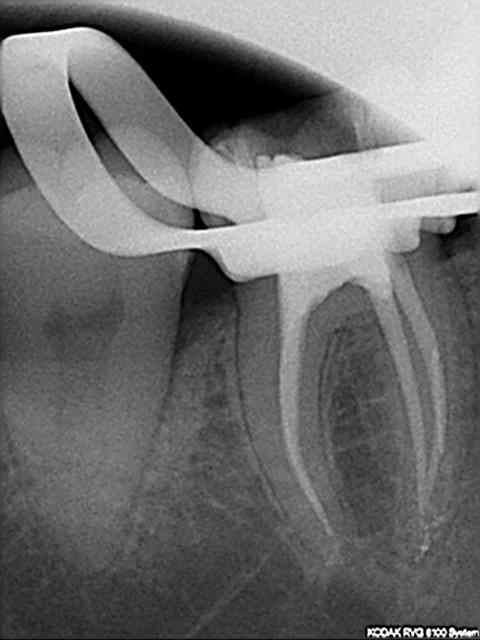

Voilà je viens de faire l'endo et de mettre la dent sous provisoire.

21/07/2008 à 19h21

radio

c'est un Mcspadden dans la mesiale?

elle a encore des symptomes la dame?